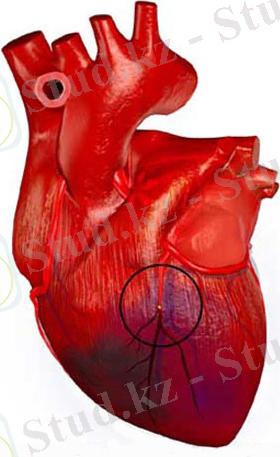

7 сурет. Миокард инфаркті.

... жалғасы8 сурет. Миокард мироскопиялық көрінісі

Венозды тоқырау айқындалмаған деңгейінде геморрагиялық инфаркт тудыруы мүмкін. Геморрагиялық инфаркттың негізгі формасы веноздық инфаркт болып саналады, соның себептері окклязия болып табылады. Миокард инфарктында коронарлық артериялардың қатты жиырылуынан немесе бүліну ошағында биологиялық белсенді заттардың ( брадикинин, гистамин, серотонин, аденозин т. б. ) жиналып қалуынан қатты ауыру сезімі болады және ол қатты қобалжу, қорқу сезімімен қабаттасады. Ауыру сезімі сол жақ қолға, жауырынға, иыққа, астыңға жаққа, тіске берілуі мүмкін. Ол жұлында ішкі ағза нейрондарынан қозудың тері мен шырышты қабықтардағы сезімтал нейрондардың аймақтарына таралуынан дамиды. Кейде клиникада миокард инфарктының ауырмайтын түрін де жиі кездесетіруге болады. Ол макрофагтарда көптеп эндогендік эндорфиндер өндірілуімен түсіндіріледі. Миокард инфарктінің ең бір ауыр асқынулары болып кардиогендік шок және өкпе ісінуі есептелінеді. Бұл кезде жүректен қан шығарылуы төмендейді, қан тамырларының жалпы шеткері кедергілік қасиеті жоғарылайды. Ол артериялық қысымды белгілі деңгейде ұстап тұруға бағытталған бейімделістік серпіліс. Бірақ артынан шеткері қан тамырлары кеңіп, олардың меже қуаты азаюдан артериялық қан қысымы күрт түсіп кетеді. Ірі ошақты миокард инфаркты жүрек аневризмасына, тромбоэмболияға, бүлінген жүрек етінің жыртылуына әкелуі мүмкін. Миокарда инфаркты кезіндегі бүлінген ет тінінің орны дәнекер тін жасушаларымен толтырылады, тыртық пайда болады. Соңғысының жиырылғыштық қасиеті, ет талшықтарына қарағанда, өте аз болғандықтан жүрек ішіндегі қысыммен артық керіліп, аневризма дамуына әкеледі. Миокард инфарктының ең қауіпті асқынуының бір түрі болып, тромбоэмболия даму мүмкіншілігі есептеледі. Бүлінген тіннен, қан тромбоциттерінен т. б. жасушалардан тіндік тромбопластин босап, тромбоциттердің адгезиясы мен агрегациясы және қан ұю үрдісінің артуынан жүрек қуыстарында қан қатпарлары пайда болады. Содан бұл қан қатпарларының бөлшектері үзіліп кетіп, эмболға айналуы мүмкін. Бұл эмбол жиі үлкен қанайналым шеңберіне тарап, орнласқан жеріне қарай ауыру малдың тез өліміне әкеледі. Жүрек қабырғасының жыртылуы үлкен трансмуралдық миокард инфарктынан болады. Бұл кезде ауыру мал өліп кетеді. Егер ол біртіндеп дамыса, қан перикард қуысына құйылып, жүректің сыртынан қысылып қалуына және ауыр кардиогендік шок дамуына әкеледі.

Миокард инфаркты - тәж қанағымының миокардтың мүқтаждығын қамтамасыз ете алмауынан дамитын миокардтың ишемиялық некрозы.